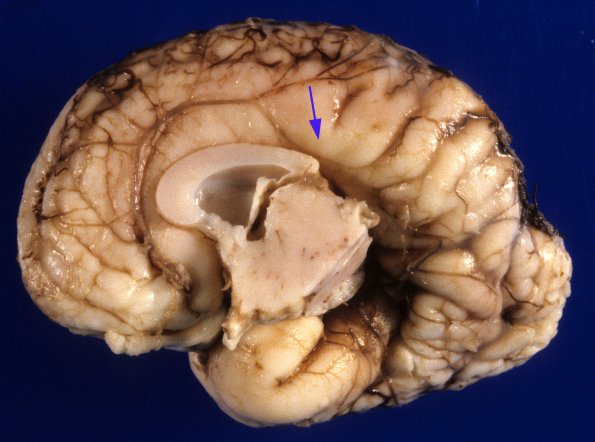

Washington University Experience | DEVELOPMENTAL MALFORMATIONS | Agenesis - Corpus Callosum | 7A2 Agenesis corpus callosum, partial, polymicrogyria (Case 7) 1A

The mesial surface shows the presence of a partial corpus callosum. The cingulate gyrus follows the intact portion of the corpus callosum and is replaced by radial gyri at the point the callosum stops (arrow). Partial loss typically involves the caudal portion and splenium of the corpus callosum.